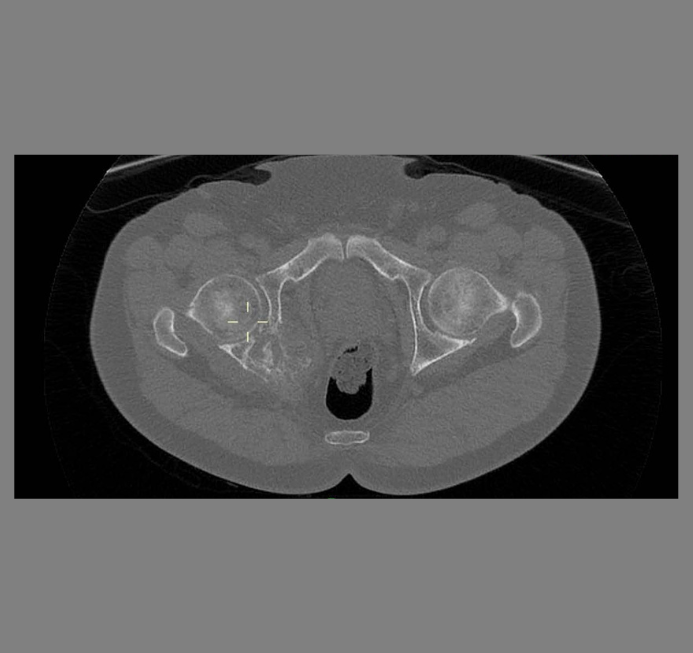

Depending on individual needs, imaging is available as part of the initial investigation. These include MRI, X-rays, CT and Ultrasound scans. Consultations are available to discuss this further.